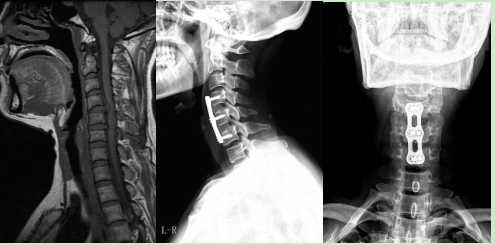

2.頸椎間盤突出行頸椎前路C4/5、C5/6椎間盤切除椎間植骨融合內(nèi)固定術(shù)